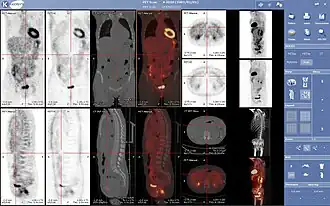

- Гибридные методы сканирования

Нормальная ПЭТ/КТ всего тела с ФДГ-18. ПЭТ/КТ всего тела обычно используется для выявления, определения стадии и последующего наблюдения за различными видами рака.

Аномальная ПЭТ/КТ всего тела с множественными метастазами рака. ПЭТ/КТ всего тела стала важным инструментом в оценке рака.